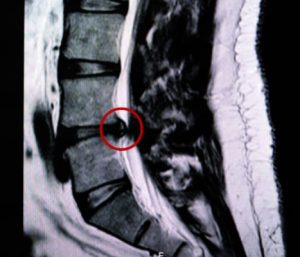

Determining whether a specific lesion is responsible for a patient’s symptoms is crucial when selecting candidates for potential spinal surgery. However, there isn’t always a direct correlation between radicular pain and lumbar disc herniation. One can exist without the other, making diagnosis complex. Both mechanical compression and inflammatory factors contribute to the pathogenesis of sciatica. Additionally, non-radicular or pseudoradicular pain can originate from the hip, sacroiliac joint, or spinal facets and may misleadingly present as pain in the lower extremity. Moreover, intermittent claudication from arterial occlusive disease can be confused with neurogenic claudication from cauda equina compression in spinal stenosis.

Historical studies highlight the complexity of these diagnoses. Hitselberger and Witten (1968) found abnormal lumbar and cervical myelographic findings in 110 out of 300 patients without symptoms of nerve root compression. Wiesel et al. (1984) reported disc herniations in 35% of asymptomatic individuals in their CT studies. Similarly, Boden et al. (1990) found herniated discs or spinal stenosis in one-third of asymptomatic individuals, with stenosis incidence increasing with age. In a long-term study, Borenstein et al. (2001) concluded that asymptomatic disc herniations did not increase the risk of developing low back pain. Conversely, Modic et al. (1995) observed normal lumbar spinal MRIs in some patients with acute lumbar radiculopathy symptoms.

Interestingly, disc herniation can sometimes appear on the side opposite to clinical symptoms (Safdarian M, et al. 2016; Ruschel LG, et al. 2021), making it a chance finding unrelated to the patient’s pain. An unwarranted decision to operate can result in removing an asymptomatic disc herniation while the true cause of pain remains untreated.

In summary, no single feature can reliably distinguish a symptomatic disc herniation from an incidental finding. This highlights the importance of a comprehensive and cautious approach in diagnosing and treating lower back pain and related symptoms. For more insights into the relationship between MRI findings and presenting symptoms in low back pain patients, check out my recent blog posts (1, & 2).